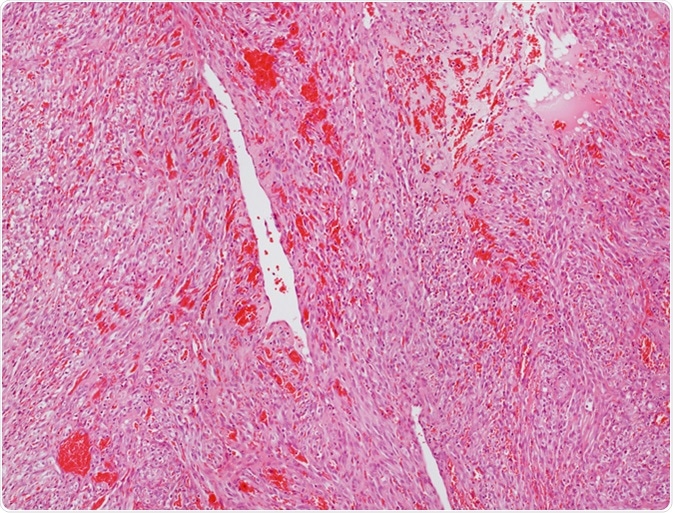

Microscope picture of an angiosarcoma. Image Credit: Convit / Shutterstock